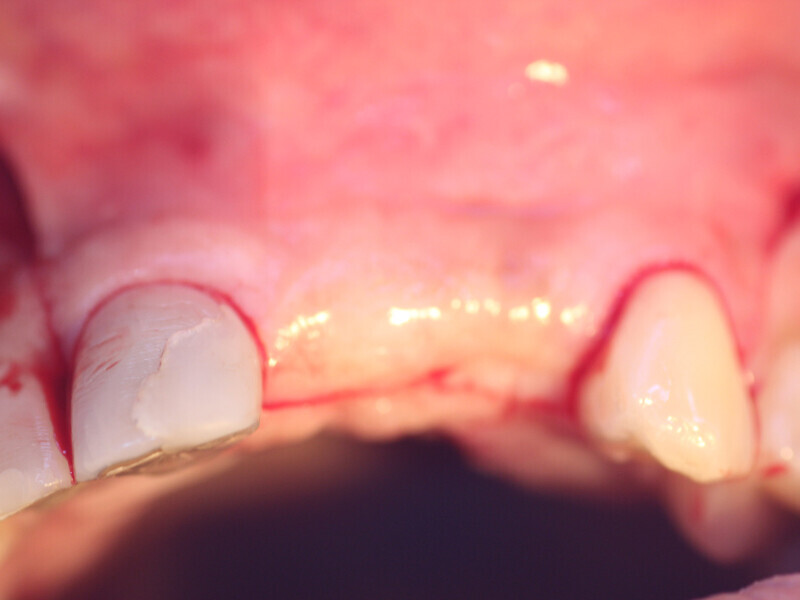

Fig. 15a: The previously deficient ridge at the left central and lateral incisors resulting from resorption following the previously extracted teeth had been augmented and is ready for implant placement following 4.5 months of graft healing.

Fig. 15b: The previously deficient ridge at the left central and lateral incisors resulting from resorption following the previously extracted teeth had been augmented and is ready for implant placement following 4.5 months of graft healing.